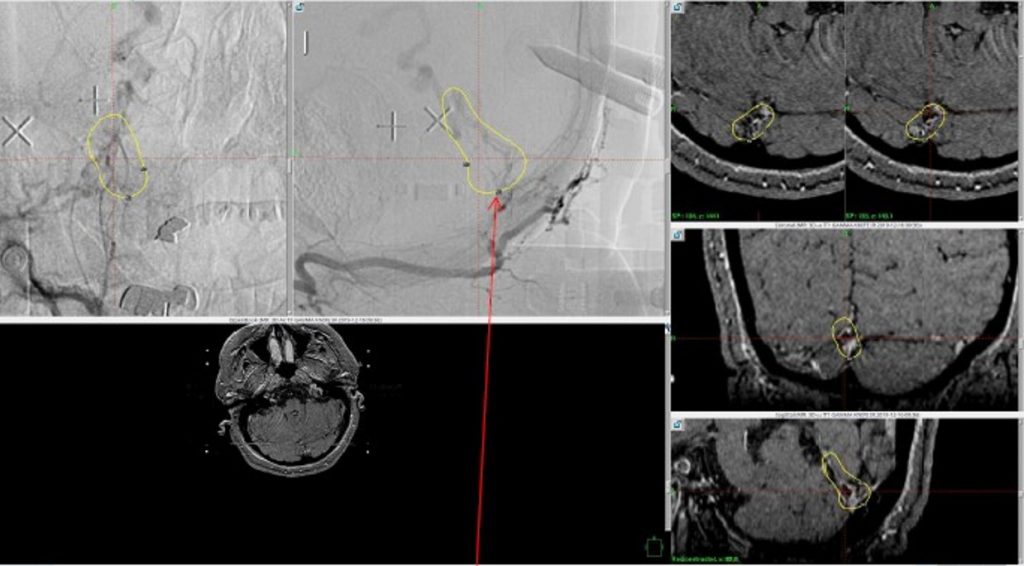

Embolization was successful at immediately reducing the pressure into the Aneurysmal Varix with greater than 90% reduction in A-V shunts. After an intensive period of critical care monitoring and care for her initial brain hemorrhage, she made a near complete recovery with mild intermittent left sided paresthesias and generalized deconditioning. After receiving inpatient and outpatient Acute Rehabilitation, Physical, and Occupational therapy, she completely recovered all of her Activities of Daily Living (ADLs) at 3 months and achieved an modified Rankin Scale (mRS) of 0. On follow-up angiography, small residual low flow A-V shunts were identified and targeted for Gamma Knife Radiosurgery (Figure 5 and 6).

Figure 6. MRI and Catheter Angiograms precisely localize the residual A-V shunts vessels to perform Gamma-Knife Radiosurgery to deliver therapeutic doses to the targets.